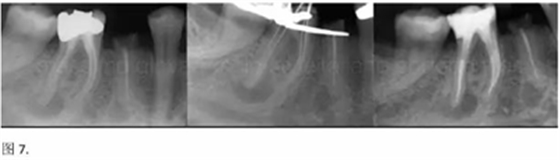

開髓后預敞、探查根管、建立直線通路是根管機械預備的第一步。在這些階段中,醫(yī)生可能會經(jīng)常遇到一些困難。這些難題包括器械折斷、臺階形成、根管歧坡或根管拉直、帶狀穿孔、根尖穿孔、根尖肘形、根尖堵塞。所有這些錯誤可導致根管系統(tǒng)清潔不完善從而降低牙髓治療成功率。

本文的目的是描述一種旨在優(yōu)化根管根尖部分預備的預敞技術(shù)。根管頸部或冠方的早期預敞對于減少初尖銼直徑和根尖部根管直徑之間的差異至關(guān)重要。大量研究表明,手用或機用器械預敞根管能顯著減少器械折斷的發(fā)生率。